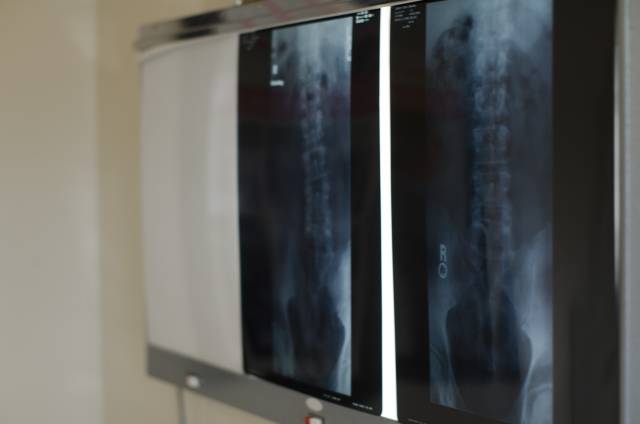

今回は、昔、自分が整形外科で勤務していた時にあった話です。

その理由として、この方はポリオによる小児麻痺の後遺症で、下肢の麻痺もある方だったので、他の人よりも自分はハンデのある体という認識があり、リハビリをしてもらう相手はしっかりと選ばなければならいという思いがあったようです。

こんな単純な話でも理由を脊柱管狭窄症やヘルニアなど病名のせいにされてしまったり、後遺症があるからとか、年をとったからとか、治らない理由がこじれていくと本当に治らない症状のように思い込んでいくんですよね。